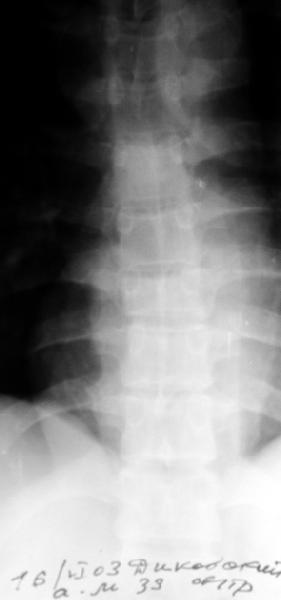

Перелом IX грудного позвонка |

Мужчина 39 лет, перевернулся в машине 12 июня. Клинически неврологии нет. Нужна ли репозиция и оперативная фиксация этого повреждения? Если нет, то как вести? Спасибо заранее.